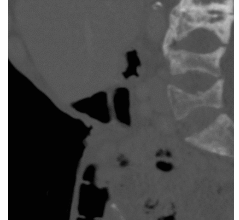

Cervico Facial Actinomycotic Osteomyelitis : A Single Center Experience

Global Journal of Pathology & Laboratory Medicine Volume 2, Issue 1, July, 36-46 Received: April 5, 2023, Reviewed: April 10,…